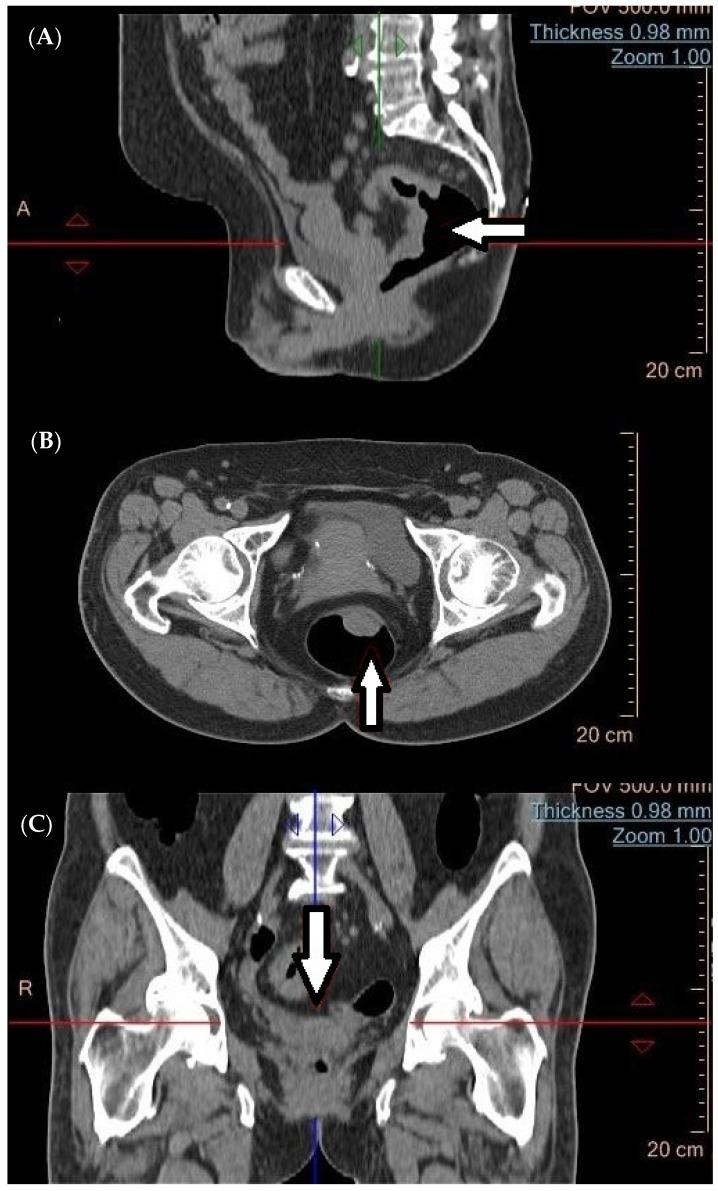

Rectal cancer (RC) is a prevalent malignancy with significant morbidity and mortality rates. The accurate staging of RC is crucial for optimal treatment planning and patient outcomes. This review aims to summarize the current literature on imaging and metabolic diagnostic methods used in the stage assessment of RC. Various imaging modalities play a pivotal role in the initial evaluation and staging of RC. These include magnetic resonance imaging (MRI), computed tomography (CT), and endorectal ultrasound (ERUS). MRI has emerged as the gold standard for local staging due to its superior soft tissue resolution and ability to assess tumor invasion depth, lymph node involvement, and the presence of extramural vascular invasion. CT imaging provides valuable information about distant metastases and helps determine the feasibility of surgical resection. ERUS aids in assessing tumor depth, perirectal lymph nodes, and sphincter involvement. Understanding the strengths and limitations of each diagnostic modality is essential for accurate staging and treatment decisions in RC. Furthermore, the integration of multiple imaging and metabolic methods, such as PET/CT or PET/MRI, can enhance diagnostic accuracy and provide valuable prognostic information. Thus, a literature review was conducted to investigate and assess the effectiveness and accuracy of diagnostic methods, both imaging and metabolic, in the stage assessment of RC.

直肠癌(RC)是一种常见的恶性肿瘤,发病率和死亡率都很高。准确的直肠癌分期对于优化治疗方案和患者预后至关重要。本综述旨在总结目前关于直肠癌分期评估中使用的影像学和代谢诊断方法的文献。各种影像学检查在直肠癌的初始评估和分期中起着关键作用。这些检查包括磁共振成像(MRI)、计算机断层扫描(CT)和直肠内超声(ERUS)。由于MRI具有卓越的软组织分辨率以及评估肿瘤浸润深度、淋巴结受累情况和壁外血管侵犯的能力,它已成为局部分期的金标准。CT成像提供了有关远处转移的有价值信息,并有助于确定手术切除的可行性。ERUS有助于评估肿瘤深度、直肠周围淋巴结和括约肌受累情况。了解每种诊断方法的优缺点对于直肠癌的准确分期和治疗决策至关重要。此外,整合多种影像学和代谢方法,如PET/CT或PET/MRI,可以提高诊断准确性并提供有价值的预后信息。因此,我们进行了一项文献综述,以研究和评估影像学和代谢诊断方法在直肠癌分期评估中的有效性和准确性。